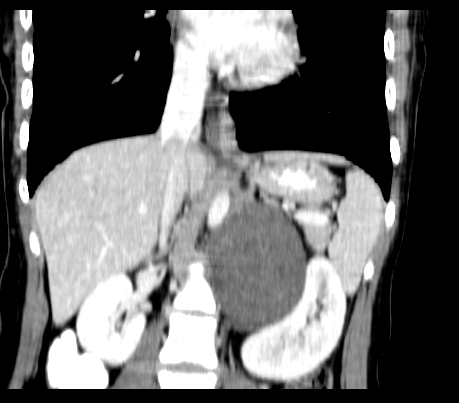

动脉期

静脉期